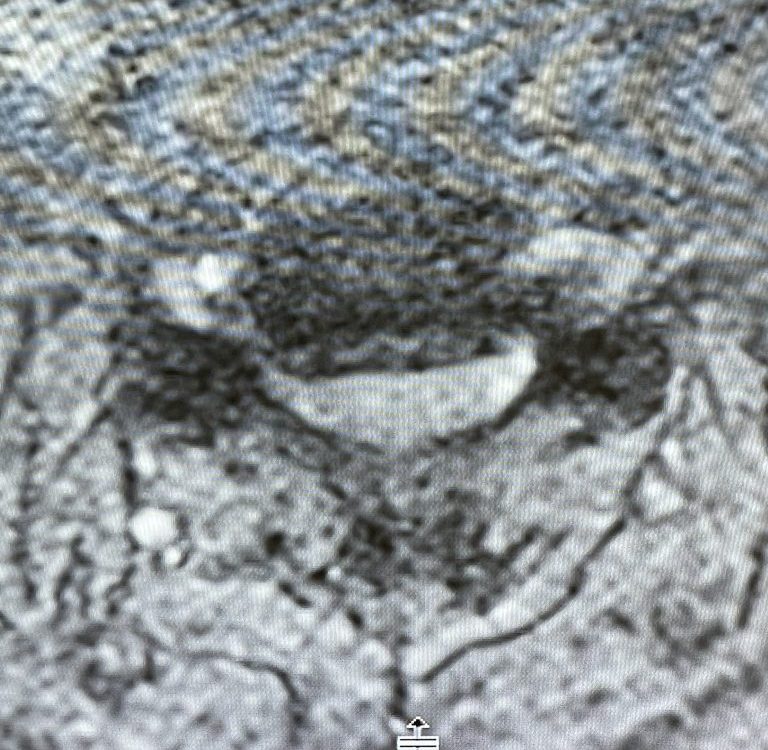

Nervous tissue is soft. The thecal sac is surrounded by a rigid bony ring which forms the spinal canal. Any mass that fills the very small […]